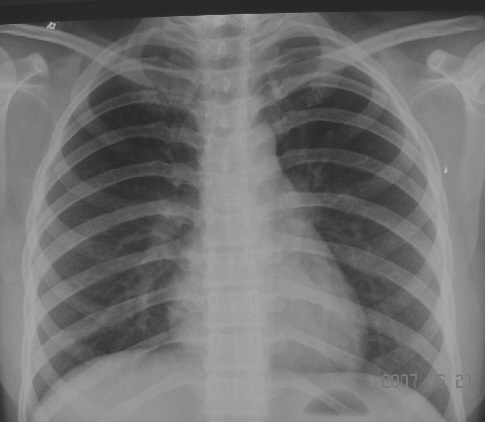

女,18y,起病高热,无咳嗽,咳痰。

2006年11月第一次胸片